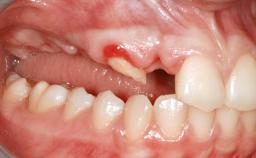

A 45-year-old woman with a completely edentulous maxilla was referred to evaluate the possibility of rehabilitation with an implant-supported prosthesis. This patient was healthy and a non-smoker. She had been wearing a maxillary complete denture opposing a natural mandibular dentition since her twenties. This situation had resulted in progressive resorption of the alveolar ridge, repeatedly creating a need for relining the denture. Twenty years later, despite multiple adaptations and the use of “glues” the denture was unstable and causing the patient psychological and functional discomfort.

Soft Tissue Anatomy Intact Defective

Bone Volume Horizontally and vertically sufficient Horizontally deficient Deficient vertically or deficient vertically AND horizontally